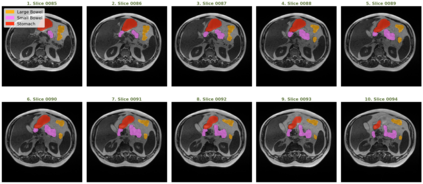

Gastro-Intestinal Tract cancer is considered a fatal malignant condition of the organs in the GI tract. Due to its fatality, there is an urgent need for medical image segmentation techniques to segment organs to reduce the treatment time and enhance the treatment. Traditional segmentation techniques rely upon handcrafted features and are computationally expensive and inefficient. Vision Transformers have gained immense popularity in many image classification and segmentation tasks. To address this problem from a transformers' perspective, we introduced a hybrid CNN-transformer architecture to segment the different organs from an image. The proposed solution is robust, scalable, and computationally efficient, with a Dice and Jaccard coefficient of 0.79 and 0.72, respectively. The proposed solution also depicts the essence of deep learning-based automation to improve the effectiveness of the treatment

翻译:胃内肠道癌被认为是GI大片器官致命恶性病,由于其致命性,迫切需要医疗图象分解技术,以便分器官减少治疗时间,加强治疗;传统分解技术依靠手工制作的特征,计算成本低,效率低;许多图像分类和分解任务中,视觉变形器受到极大欢迎。从变压器的角度来看,为了解决这一问题,我们引入了混合型CNN-传输结构,将不同器官与图像分割开来。 拟议的解决办法是稳健、可缩放和计算效率高的,Dice和Jacccard系数分别为0.79和0.72。 拟议的解决办法还描述了深层学习自动化的本质,以提高治疗的效果。